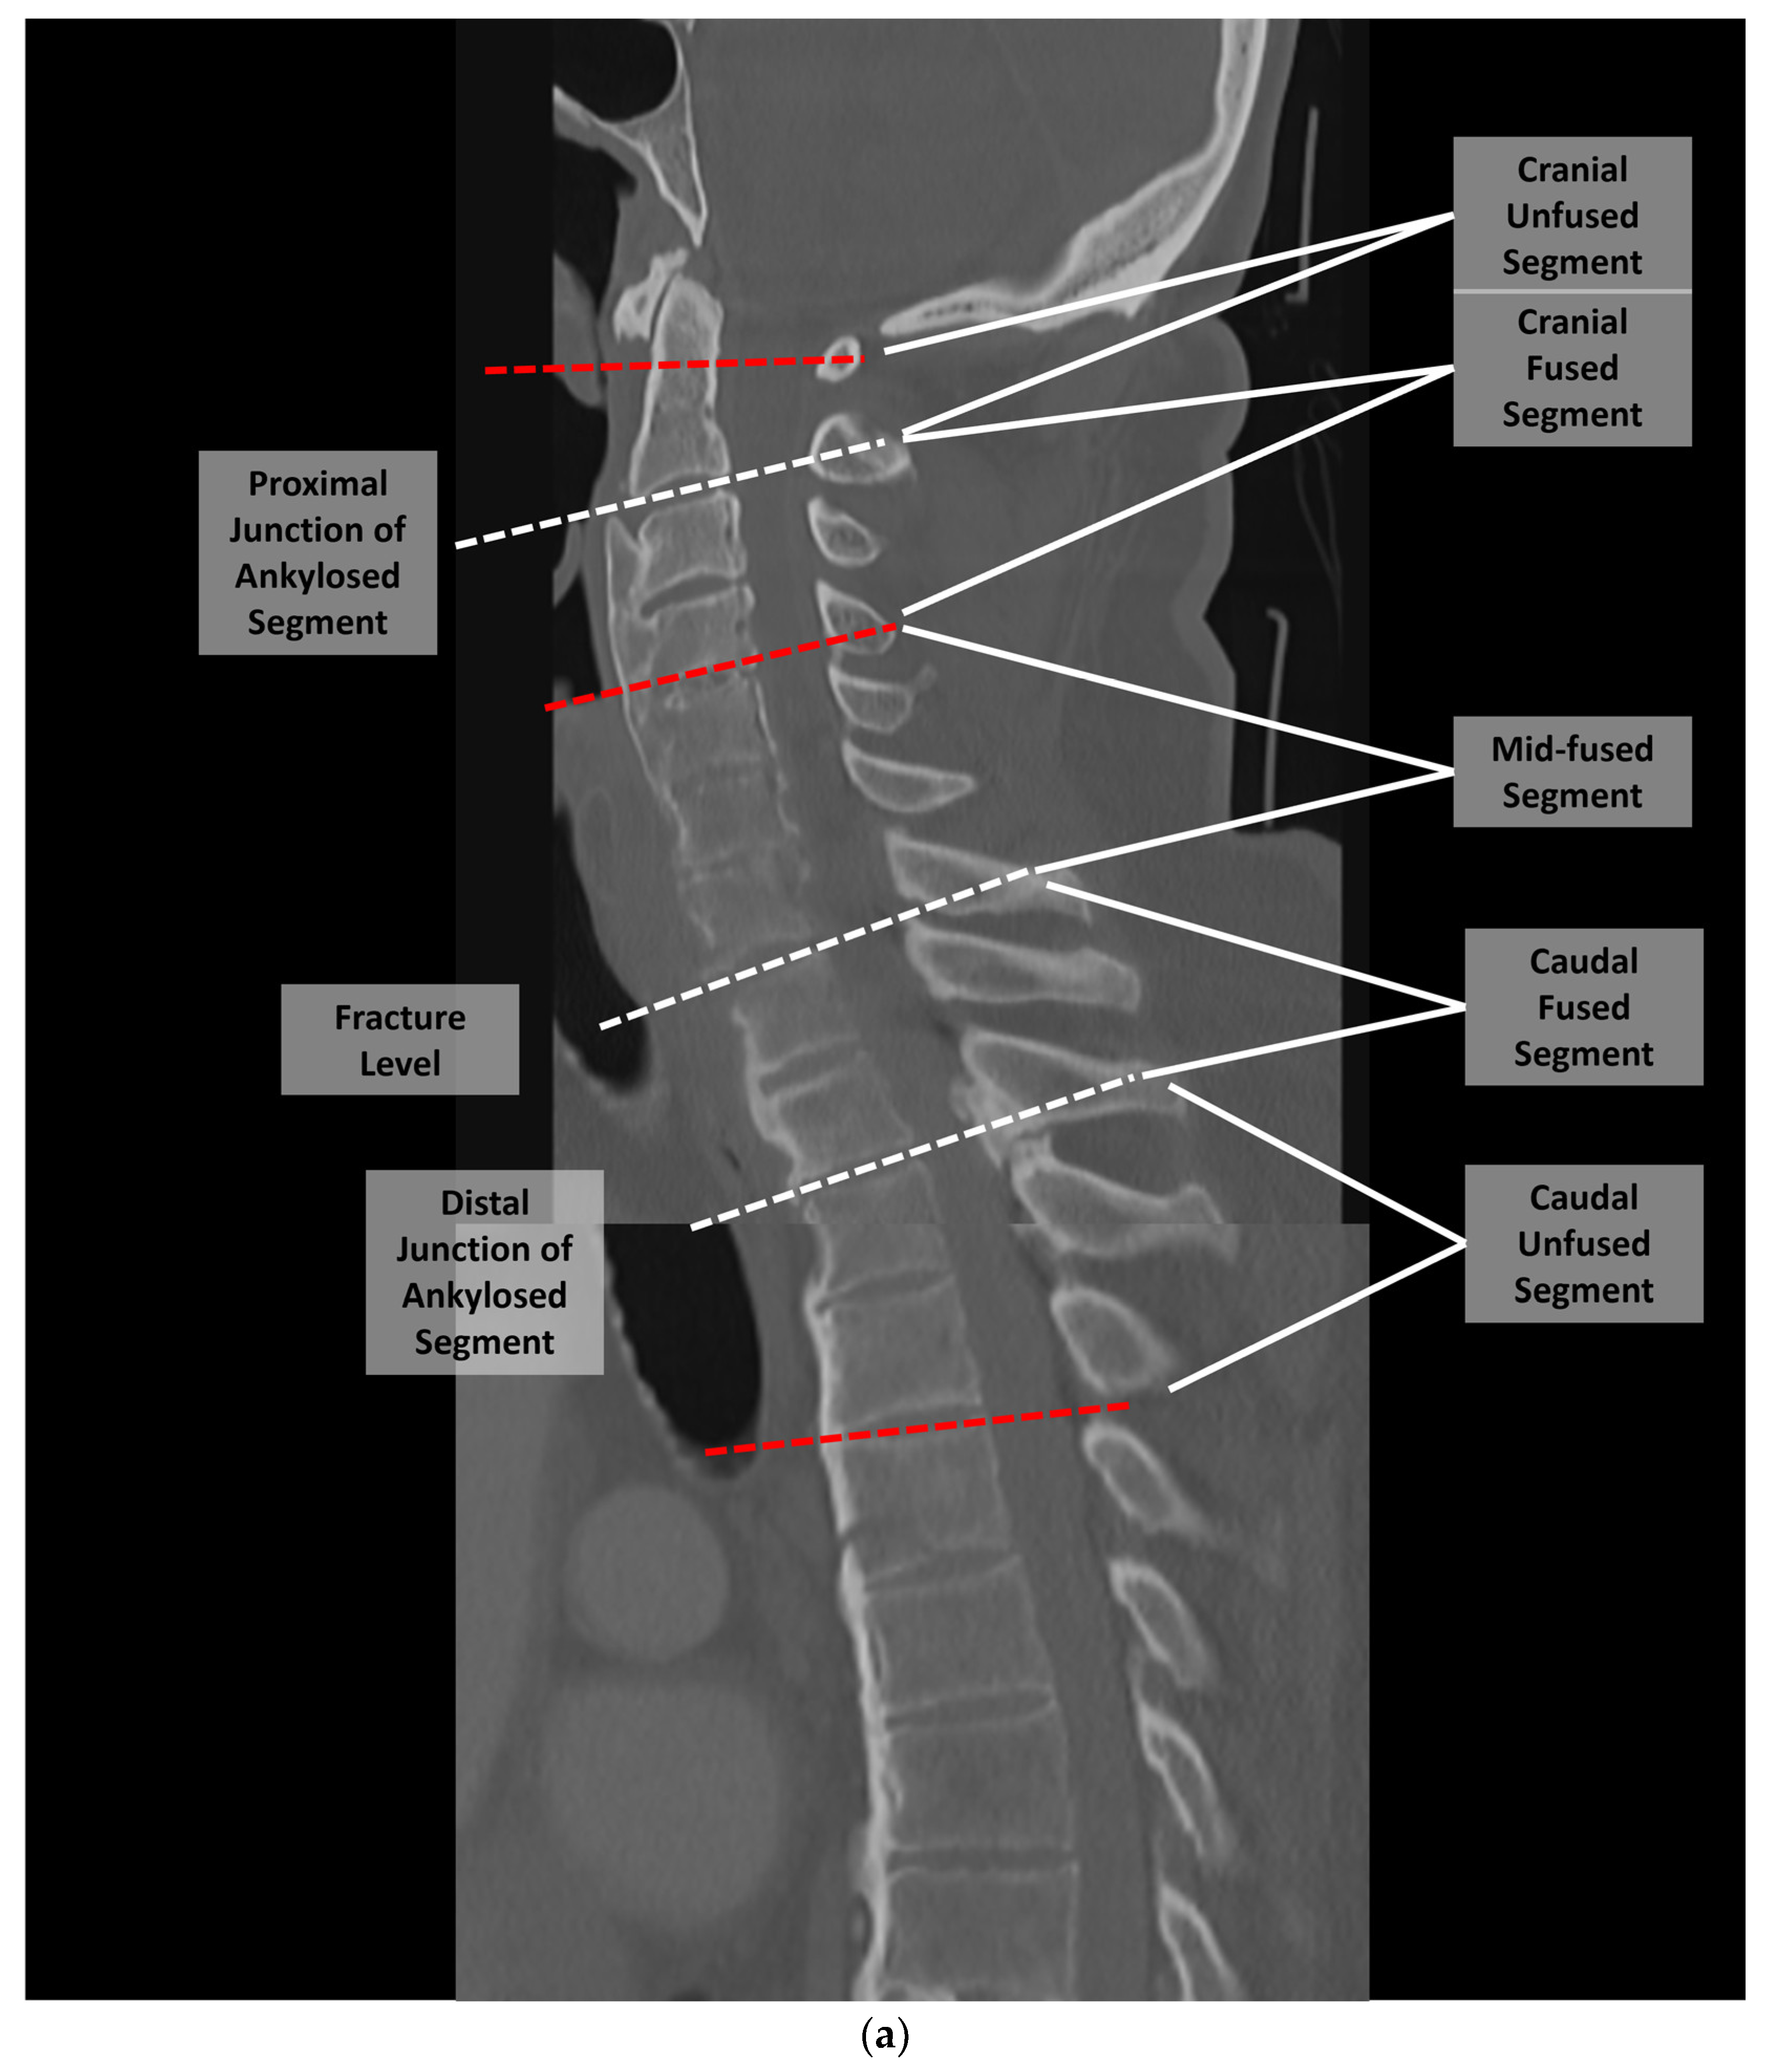

2. Materials and Methods